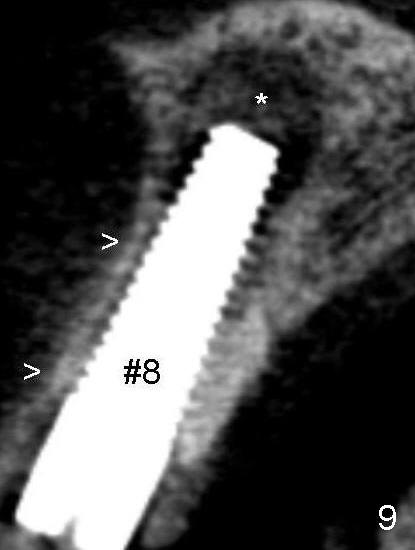

Fifty-five-year-old lady has had pain and swelling associated with #8 for a while in spite of apicoctomy in home country (Fig. 1 and 1' *, > (fistula)).  #9 is prosthodontic failure (Fig.1').  Both teeth are extracted at the same time.

Tooth #8 has an expanding radiolucency (Fig.9 * as compared to Fig.10).  Antibiotic is not going to fix this. Apico surgery will destroy the nice buccal bone (Fig.9 >). I have seen this before, The best choice is to remove the implant with a little curettage at the apex area only. Put a hemostatic gauze, absolutely no bone graft needed. Let it heal for 4 to 6 month. Then implant again.